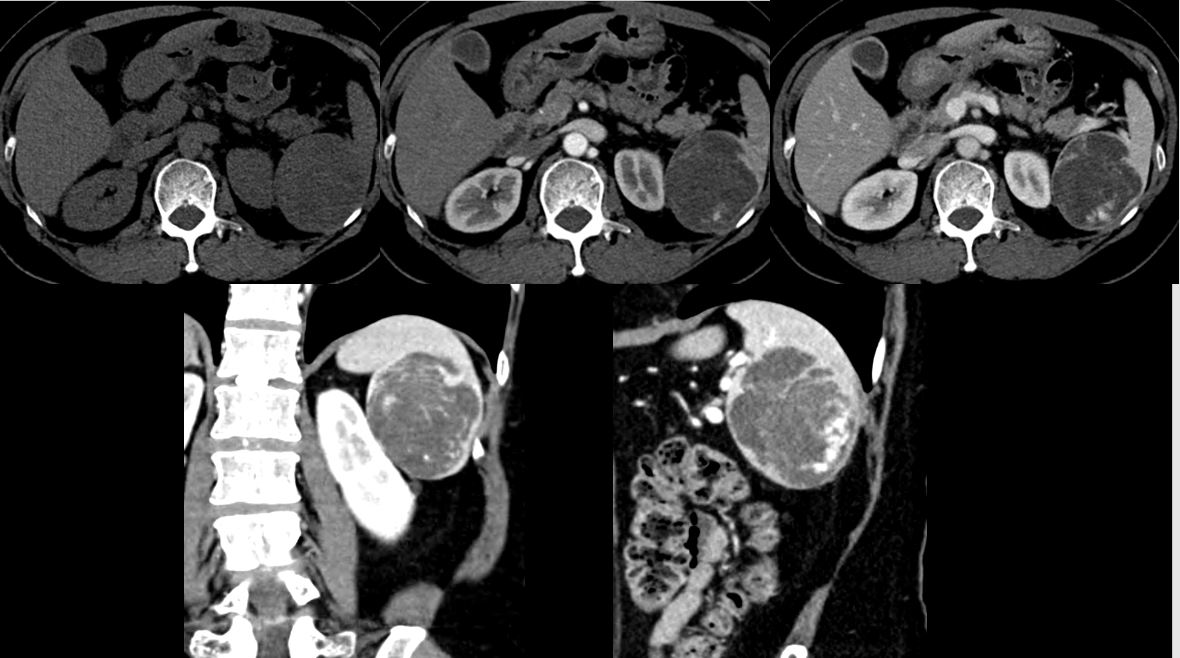

No.725

M / 68

Abnormal finding on AP-CT

ABDOMEN

»ï¼º¼¿ïº´¿ø ¹ÚÁö¿¬

CASE 2